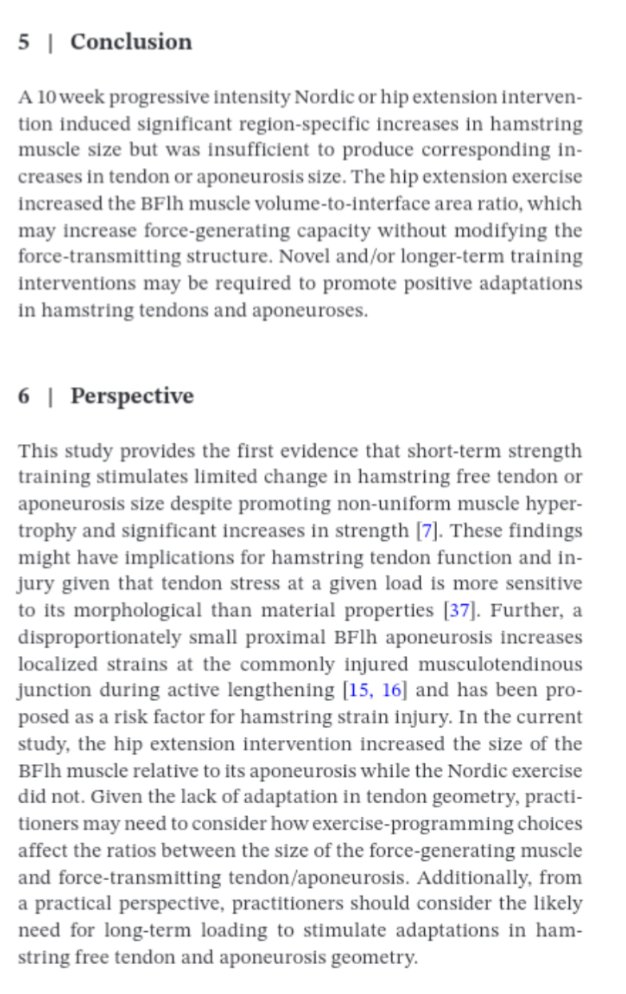

🔝"The study protocol investigated the effects of a 6-week training program using either the hip-dominant Romanian deadlift or Nordic-HE on hamstring strain injury risk factors & sprint performance" 👉S. Crawford et al, 2023 🇺🇸 BMC Series 📂Open Access: …sportsscimedrehabil.biomedcentral.com/articles/10.11…